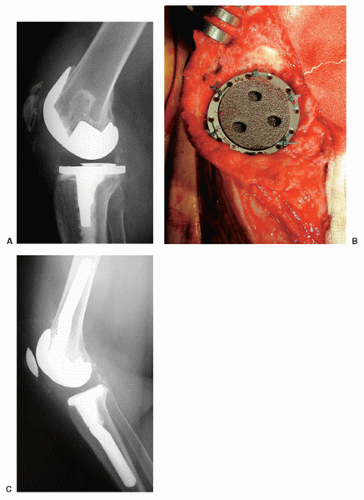

Type I, II, III 로 나뉠 수 있는데 모두 intact한 경우 I, implant는 intact하나 extensor mechanism이 작동하지 않을 때는 II, implant도 loosening 되고, implant 도 풀린 경우에는 III 로 나뉠 수 있습니다.

Type III의 경우 골질의 양에 따라 두개로 선택지를 나누어 치료를 할 수 있습니다.